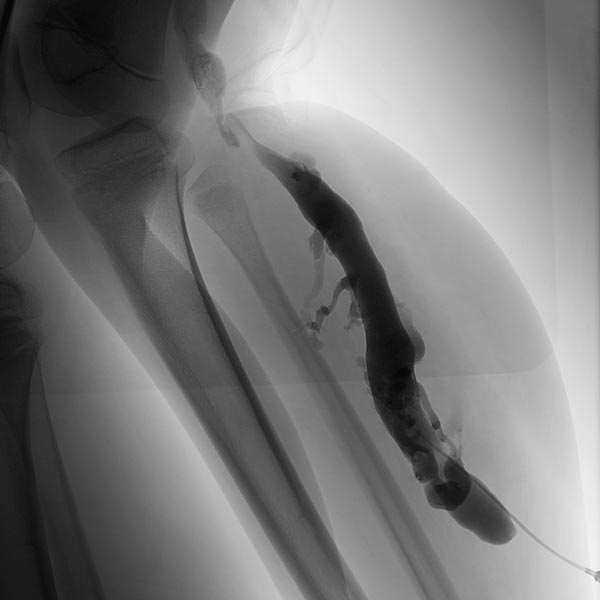

Die Phlebographie nach Direktpunktion des venösen Malformationsanteils zeigt eine großlumige Drainagevene, die in der Kniekehle mit der V. poplitea kommuniziert. Diese muss zunächst verschlossen werden, da sonst das Sklerosierungsmittel darüber abfließen könnte und potentiell eine Thrombose der tiefen Leitvenen des Beins (und eine Lungenembolie) verursachen könnte. Zudem besteht grundsätzlich ein erhöhtes Thrombembolierisiko bei der Patientin, dass durch den Verschluss deutlich vermindert werden kann.

Dazu wird zunächst über einen Einführungsdraht eine großlumige Einführungsschleuse vorgebracht, die zum Einführen der Laserfaser dient. Dieser wird über die Vene bis zum Kommunikationspunkt in der Kniekehle vorgeschoben.

Durch diese Schleuse wird eine Laserfaser zur endovaskulären Lasertherapie vorgeführt. Durch die Erhitzung des Laserstrahls kommt es zu einer massiven Reizung der Venenwand, die sich anschließend sehr schnell verschließt. Um die Laserspitze kommt es sofort zur Thrombusbildung (weiß, da als Kontrastmittelaussparung sichtbar).